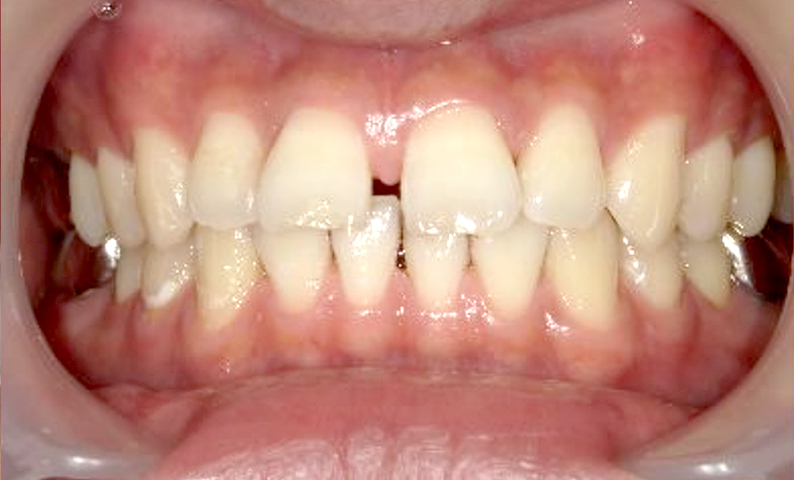

| 治療前 | 治療後 |

|---|---|

|